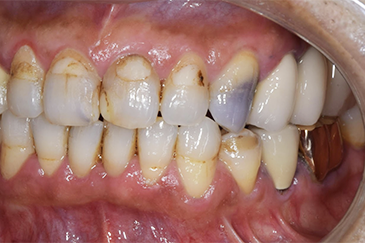

Before

途中経過

After

| 年齢・性別 | 20代・女性 |

| 主訴 | 前歯見た目気になる (右123番・左上123番) |

| 治療内容 | 右上123左上123 ジルコニアボンド |

| 治療費 | 990,000円 (ジルコニアボンド1本165,000円) |

| 治療期間 | 約2ヶ月 |

| リスク・副作用 | 歯軋りが強いと稀に割れることがある。 |